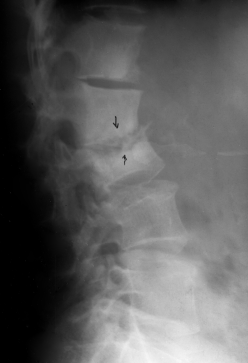

病例3,女,39岁,腰椎破坏3年,食用7个月痊愈。治疗前第2、3腰椎骨质破坏(a),有窦道流脓水。治疗后坏死灶消失,窦道愈合,骨质硬化(b).

Case 3. Repair of bone tuberculosis: female, 39 years old, 3 years old, cured with antituberculosis drugs for 7 months. Bone destruction of the 2nd and 3rd lumbar vertebrae before eating (a). The necrosis of the 2nd and 3rd lumbar vertebrae disappeared and osteosclerosis (b).